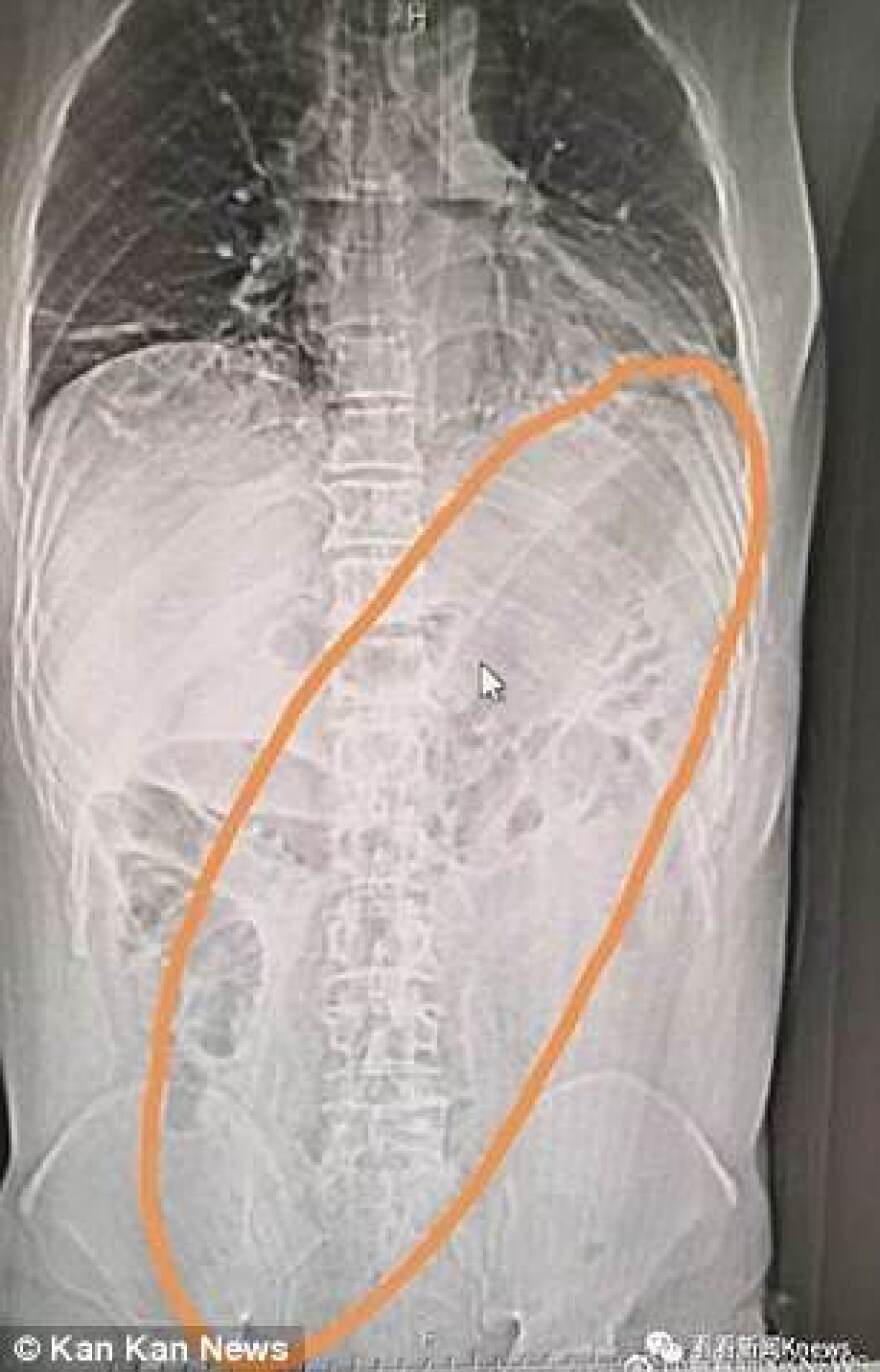

Όταν ο 50χρονος υποβλήθηκε σε ακτίνες για να διαπιστωθεί από τι πάσχει, οι γιατροί διέκριναν με μεγάλη έκπληξη ένα τεράστιο αντικείμενο να έχει κολλήσει στο έντερο το ασθενούς.

Τα παραπάνω υποστήριξε ο 50χρονος άνδρας, προκειμένου να δικαιολογήσει την... παρουσία του αντικειμένου στο παχύ του έντερο. Όποιος και αν ήταν, τέλος πάντων, ο λόγος που έβαλε τη μελιτζάνα στον πρωκτό του, το πρόβλημα δημιουργήθηκε όταν... έχασε τον έλεγχο στο... χειρισμό! Η μελιτζάνα εισχώρησε πιο βαθιά και... τα υπόλοιπα φάνηκαν στην ακτινογραφία!

Τα πειστήρια των εξετάσεων...